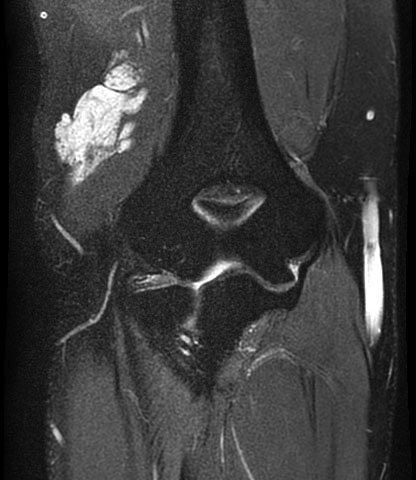

#CaseOfTheWeek‼️🥳‼️ ☢️🩻☠️Case#22☠️🩻☢️ #Mass 📲➡️➡️#Diagnosis❔❓❔ #FOAMRad #RadEd #MedEd #OrthoEd #OrthoTwitter @ssr_rwg @UWRadRes @ISSVA_org